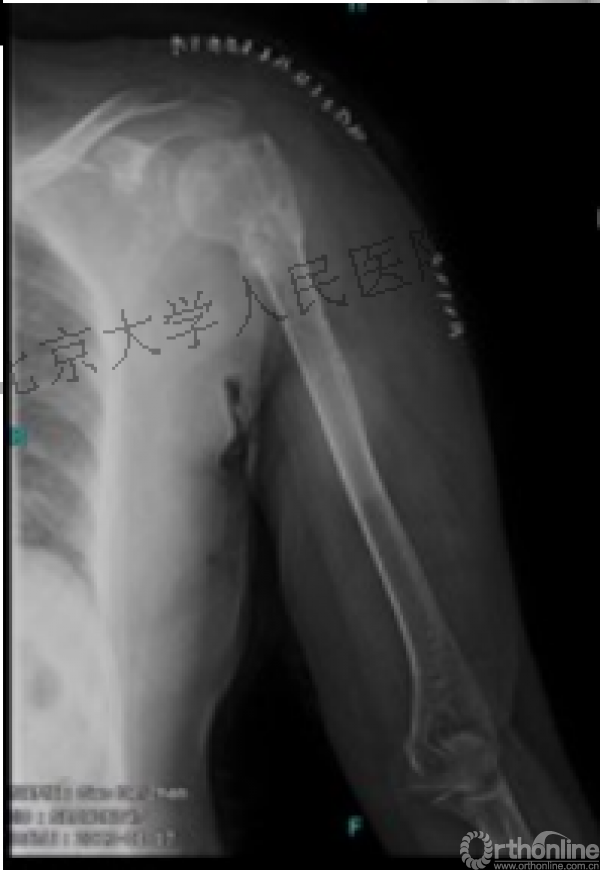

二、临床中我们常遇到类似下面的病例

内侧皮质粉碎,低位外科颈骨折,肱骨头-干角维持困难。

术后复位丢失,肱骨头内翻畸形。

能否该偏心固定(钢板)为髓内固定,增加力臂?

此时对比髓内钉是不是有很大优势?